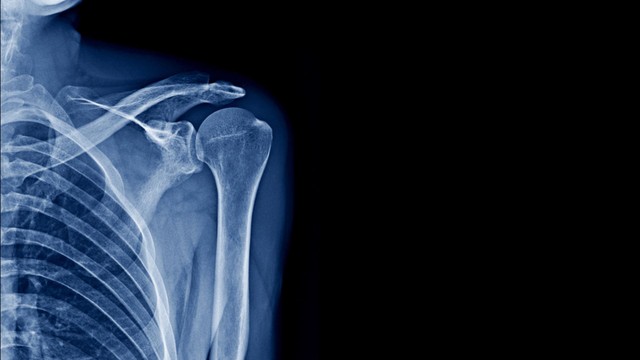

Chẩn đoán bệnh